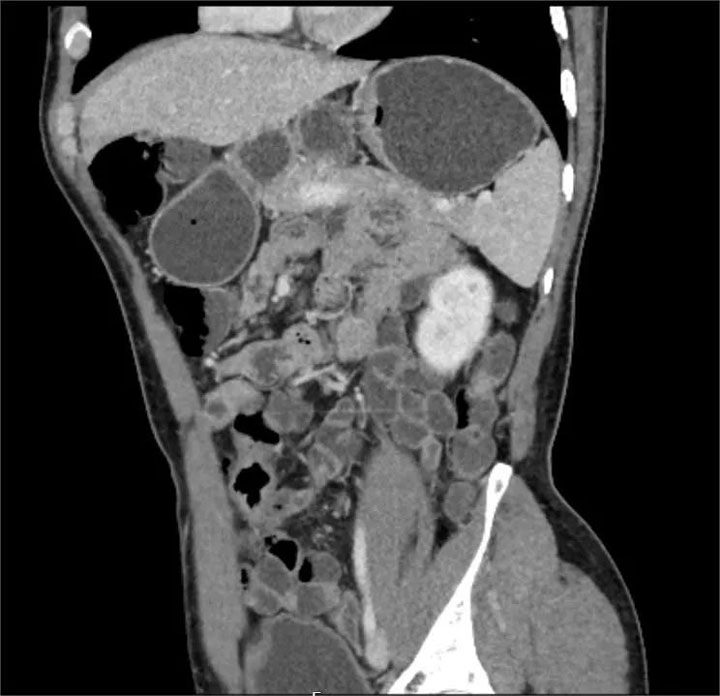

CT小肠造影(CT enterography,CTE)是患者口服或经小肠导管注入对比剂使小肠腔充盈足量对比剂后,经多排螺旋CT增强扫描,并将图像进行后处理,使肠腔、肠壁、肠系膜、腹腔内血管、后腹膜及腹内实质脏器多方位显示出来的技术。临床证明,CT小肠造影(CT enterography,CTE)可精确的判定小肠肿瘤的数目,监测出小肠早期肿瘤,可作为小肠肿瘤定位及诊断的首先检查方法。

CTE简便易行,无明显并发症,不仅能观察肠腔、肠壁、肠外淋巴结、肠系膜、肠系膜血管关系以及毗邻结构等,还可以精确显示粘膜病变、肠壁增厚及肠外并发症,可准确判断小肠肿瘤的浸润深度。适用于多种小肠病变,全腹部扫描能及时发现肿瘤转移情况,有助于临床更准确的把握肿瘤术前分期,能够为患者制定最优治疗方案,带来更好的预后。